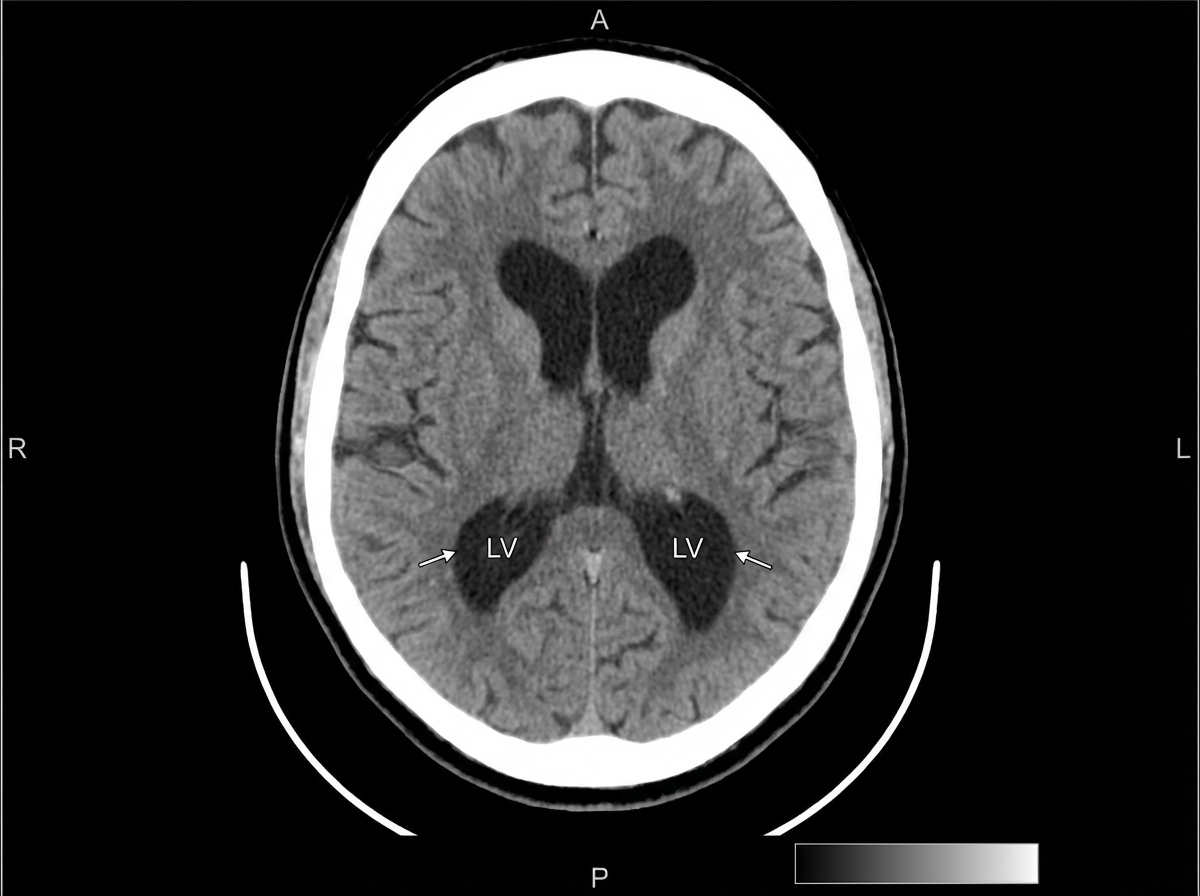

A 68-year-old woman in a wheelchair presents with her husband. She has a 12-month history of progressive difficulty in walking and maintaining balance. Her husband reports that she walks slowly, has difficulty turning, and her feet seem ‘glued to the ground’. She also has problems recalling names and details of recent events. She has no tremors, delusions, hallucinations, sleep disturbances, or head trauma. Past medical history is significant for essential hypertension treated with losartan and urinary incontinence, for which she takes oxybutynin. On physical examination, her vital signs include: temperature 37.0°C (98.6°F), blood pressure 130/70 mm Hg, and pulse 80/min. On neurologic examination, her gait is slow, with short steps and poor foot clearance. A head CT is shown. The patient undergoes a lumbar puncture to remove 50 ml of cerebrospinal fluid, which transiently improves her gait for the next 3 days. What is the next step in the management of this patient?